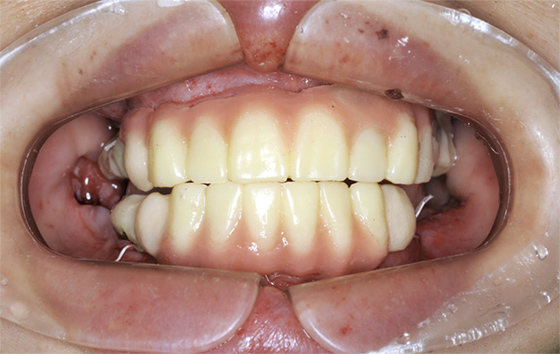

40代女性。歯科治療恐怖症で歯医者に通えず、噛み合わせが崩壊してしまい、オールオン4で再建した症例です。

この患者様の場合、治療後半年後のレントゲン写真を見ると、骨とインプラントがしっかりと結合している様子が確認できたので、最終的な人工歯を装着しました。

人工歯はネジでインプラントに固定してありますので、万が一破損などの場合でも、専用のドライバーで外して修理が可能です。

オールオン4では、失われた歯茎も人工的に作りますので、お口の張りも回復させることができ、自然な美しい笑顔を作ることができます。